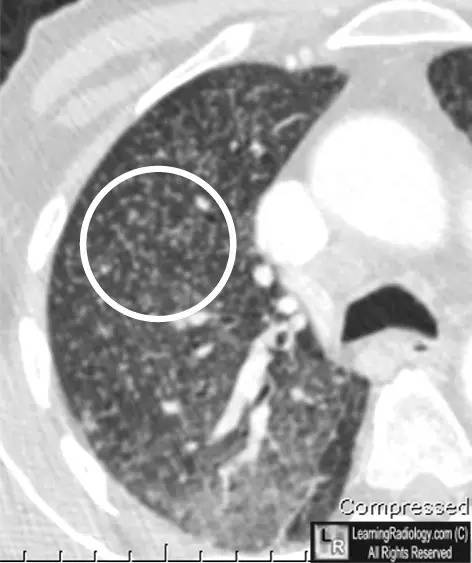

右胸CT轴位扫描特写

上图:两肺弥漫性粟粒结节

下图:局部特写图(白圆圈内)